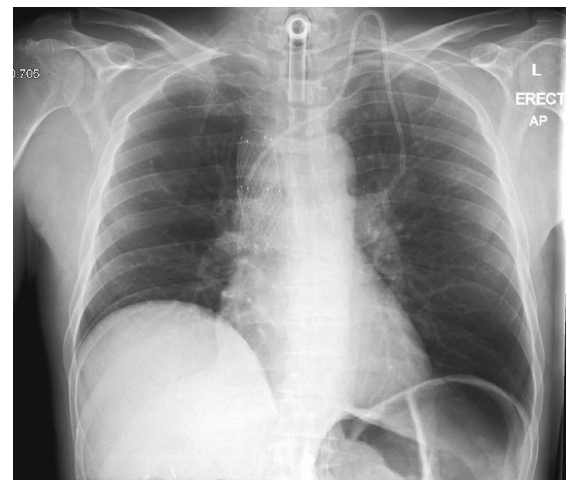

2. Armoured tracheostomy tube (Case courtesy of Daniel J Bell, Radiopaedia.org, rID:149862)